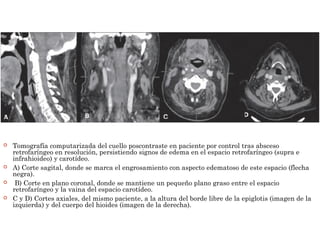

 Tomografía computarizada del cuello poscontraste en paciente por control tras absceso

retrofaríngeo en resolución, persistiendo signos de edema en el espacio retrofaríngeo (supra e

infrahioideo) y carotídeo.

 A) Corte sagital, donde se marca el engrosamiento con aspecto edematoso de este espacio (flecha

negra).

 B) Corte en plano coronal, donde se mantiene un pequeño plano graso entre el espacio

retrofaríngeo y la vaina del espacio carotídeo.

 C y D) Cortes axiales, del mismo paciente, a la altura del borde libre de la epiglotis (imagen de la

izquierda) y del cuerpo del hioides (imagen de la derecha).